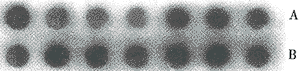

图4 PDGF-AAmRNA斑点杂交图(A:10 μl,B:20 μl)

图5 PDGF-BBmRNA斑点杂交图(A:10 μl,B:20 μl)

2.4 PDGF-AA和-BB mRNA的表达:与对照相比大鼠深度烫伤后1 d起局部组织中PDGF-AA的mRNA表达水平就达高峰,然后略有下降但仍不低于对照,至伤后7 d又有升高,随后再次下降趋于平稳;而-BB mRNA的表达水平于伤后1 d也升高,在伤后3 d有一峰值,以后略有下降,至伤后14 d起又有所升高,且要高于第一个峰值并维持至伤后28 d。伤后各时相点PDGF-BB mRNA的表达水平都高于-AA mRNA的表达水平。见图3~5。